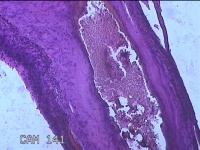

右侧肘后包块

性别

男

年龄

59岁

临床诊断

脂肪瘤

一般病史

发现右侧肘后包块1年余,无明显疼痛及不适。

标本名称

大体所见

灰白暗红色肿物1.3x0.5x0.3cm一个,表面糜烂。